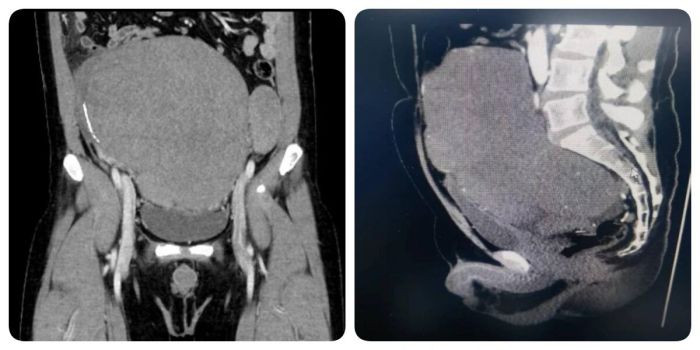

近日,在中山一院贵州医院(贵医附院贵安院区)党委书记、执行院长、泌尿外科学科带头人孙祥宙指导下,在科主任李彦锋支持下,主任医师沈俊带领主治医生张卫军、梁大廷、申开文为一名患者实施盆腔巨大肿瘤切除术,将重达约13公斤、直径25厘米的肿瘤完整摘除,用精湛医术为患者重燃生命之光。

沈俊介绍,盆腔作为人体腹腔深部的“生命枢纽”,密布着血管、神经及生殖泌尿关键器官,一旦此处滋生巨大肿瘤,便如一颗潜藏的“定时炸弹”,不仅压迫周围组织引发剧烈疼痛、排尿排便障碍,更可能危及生命。该患者入院时,盆腔肿瘤已导致其下腹部明显隆起,伴随持续性腹痛、尿频尿急等症状,生活质量严重下降。经全面检查,肿瘤与髂血管、输尿管等重要结构紧密粘连,手术切除难度极高,稍有不慎便可能引发大出血、器官损伤等严重并发症。

手术当日,在麻醉科团队的精准配合下,沈俊凭借丰富的临床经验,小心翼翼地逐层切开腹部,精准避开重要血管神经,对与肿瘤粘连的组织进行细致分离。术中,肿瘤血供丰富,并且侵犯了膀胱壁及直肠前壁狄氏筋膜,操作空间极度狭小,每一个动作都考验着医生的耐心与精准度。团队成员默契协作、沉着应对,每一个动作都力求精准,历经7小时的奋战,成功将这颗困扰患者的巨大肿瘤完整切除,并彻底止血、关闭切口。